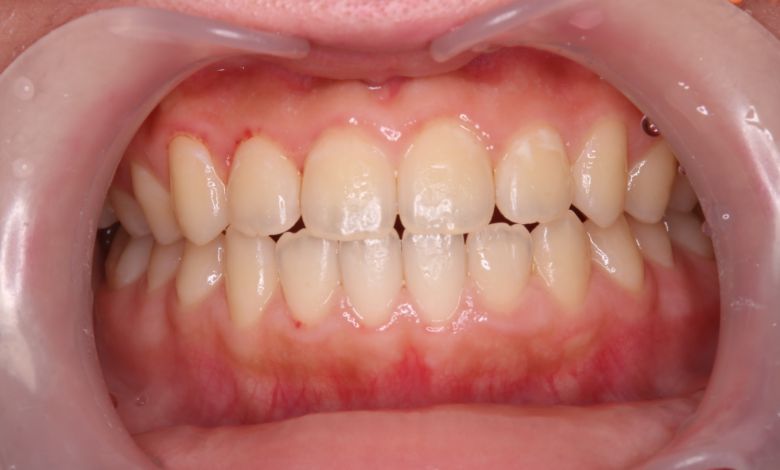

正常な咬合関係が確立され、前歯の自然なアーチと歯軸も整い、歯列全体が滑らかなカーブを描く美しい歯並びに

上下の歯がしっかりと噛み合う、美しい咬合(こうごう)が得られた

精密検査の結果、当院では抜歯を行わず、歯列弓の拡大によってスペースを確保し、非抜歯での矯正治療を選択しました。歯列の叢生(ガタガタ)は解消され、機能的かつ審美的に優れた咬合が得られました。